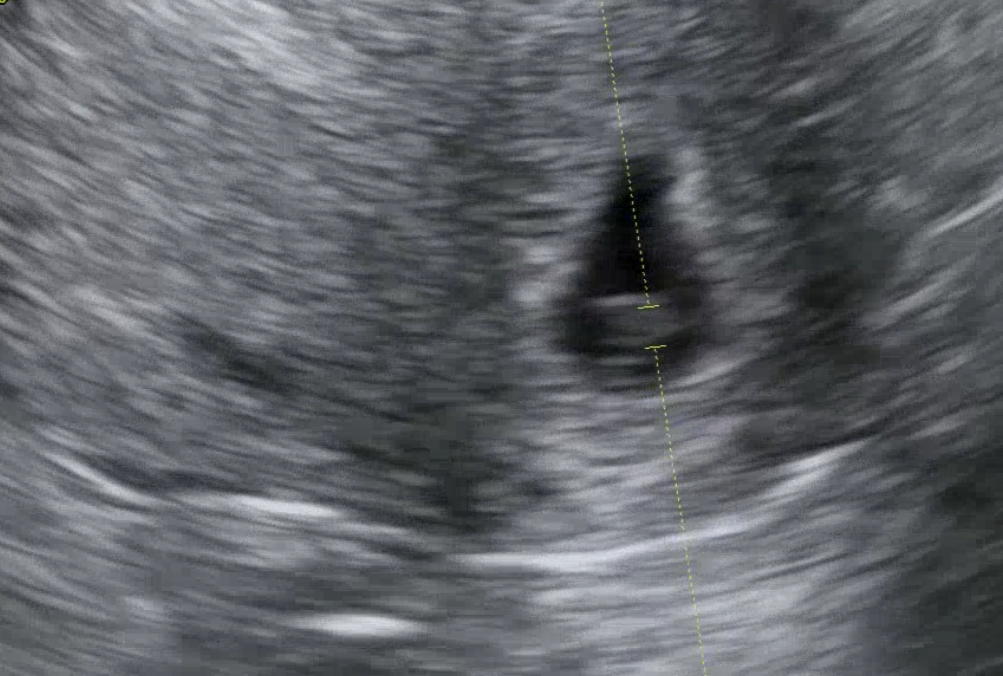

5주 4일 차 병원에 다녀왔다. 걱정하던 것이 무색하게 아기집도 보이고 난황도 보이고 심지어 아기 심장이 깜박거리는 것까지 보고 왔다. 드라마나 영화에서처럼 감동이 물밀듯 밀려오진 않았지만 건강하게 잘 크고 있는 것 같아서 걱정이 덜었다 하는 마음이었다.